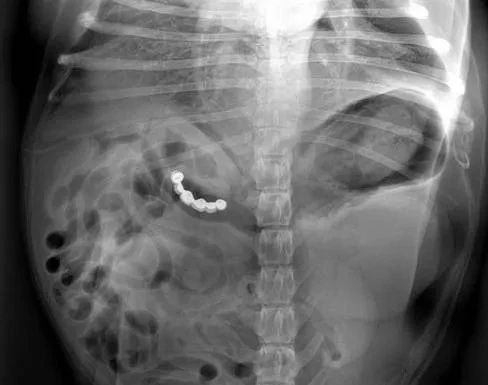

有宠物医院专门PO出了一些X光影像来提醒铲屎官注意狗狗异食行为,看看它们吞下的东西简直让人瞠目结舌。

主人从这只狗狗肚子里取出了1.29美金(硬币),知道帮主人存钱了,真贴心!